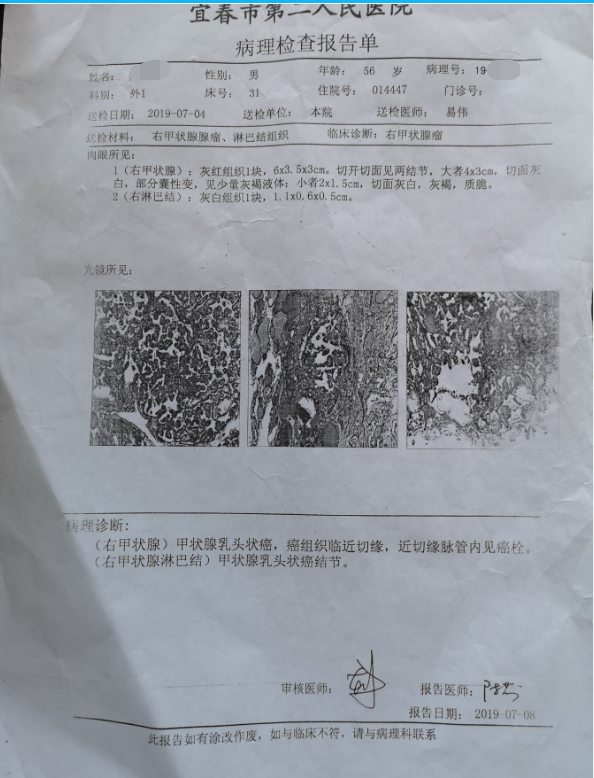

甲状腺癌再次手术

病例2 右2,右4R区,左6区残留,颈部切口清扫,未开胸